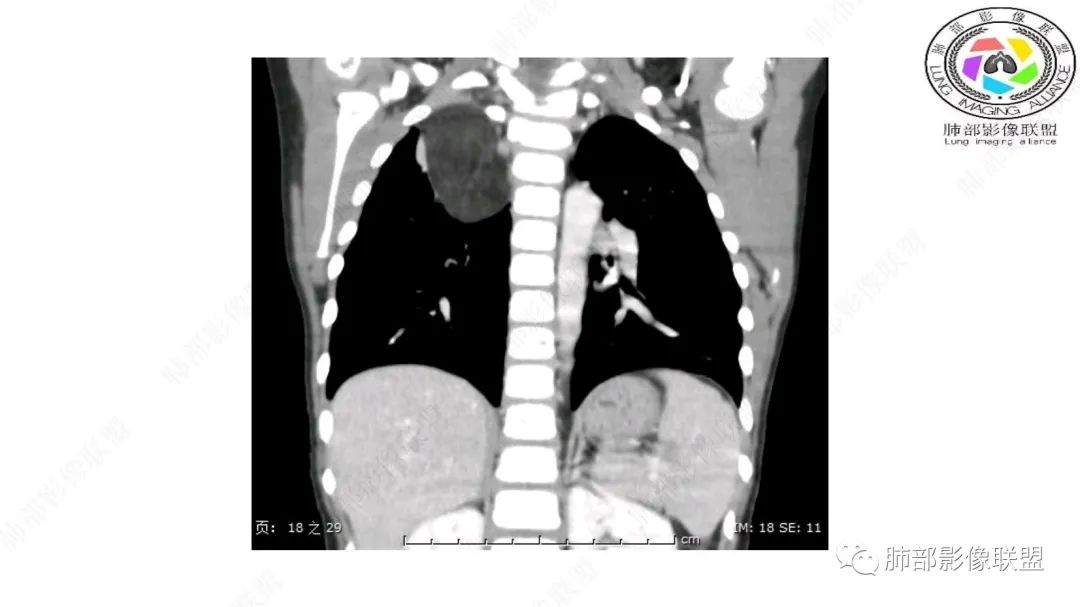

三岁小儿,右侧纵隔巨大脂肪密度肿块,肺动脉穿行其中,密度欠均匀,未见明确实性成分,纵隔脂肪母细胞瘤,冬眠瘤鉴别纵隔脂肪增多症(多弥漫对称)。

幼儿,右上纵隔团块状脂肪密度影,边缘清晰,内可见血管及支气管穿行,考虑脂肪瘤,鉴别畸胎瘤。

幼儿,右上纵膈团块,脂肪密度,内见分隔,增强病灶内见血管穿行,结合患者年龄,考虑脂肪母细胞瘤,鉴别脂肪瘤。

病灶属于交界区,主体位于肺内,占位效应明显,前方突入胸壁,胸腺受压变形,胸膜显示欠清楚;病灶包绕上叶肺动脉;似乎有体动脉供血。符合肺内的点:包绕上叶肺动脉分支;符合纵隔的点:前方似乎突入胸壁,与胸腺关系比较密切,但是与上腔静脉的关系提示病灶不支持纵隔来源,前纵隔的常规会将上腔静脉受压后移、外移,这是不符合的。

1.右上肺-纵隔交界区巨块影,主体位于右肺一侧,紧贴胸腺、头臂干、右锁骨下动脉、上腔静脉、奇静脉等,不能分离,但病灶整体边界清楚。注意上述相邻腔静脉等结构未见受压变形,纵隔亦未见明显向左推移,至少提示两点:

1)病灶相当柔软。

2)位于纵隔内或纵隔胸膜的可能性较小,因为受纵隔胸膜反作用力影响不明显。

2.肺动脉穿行也许是肺内来源最重要支持点!

CT扫描对脂肪类肿瘤常有独到价值。肿块孤立、边界清楚,未见周围浸润,较均匀脂肪样低密度,高度提示为良性!

发生于成人为脂肪瘤表现,婴幼儿自然会想到脂肪母细胞瘤。两者生物学行为并无本质区别。